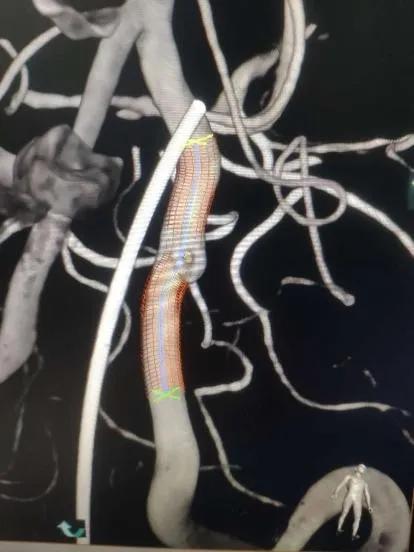

静脉肝素化,T-track支架导管微导丝导引下超选跨病变部位置入右侧大脑后动脉段。予以4.0×25mm Tubridge®血管重建装置于左椎动脉脊髓前动脉开口处近侧锚定缓慢释放,支架打开良好,贴壁完全。

支架置入过程